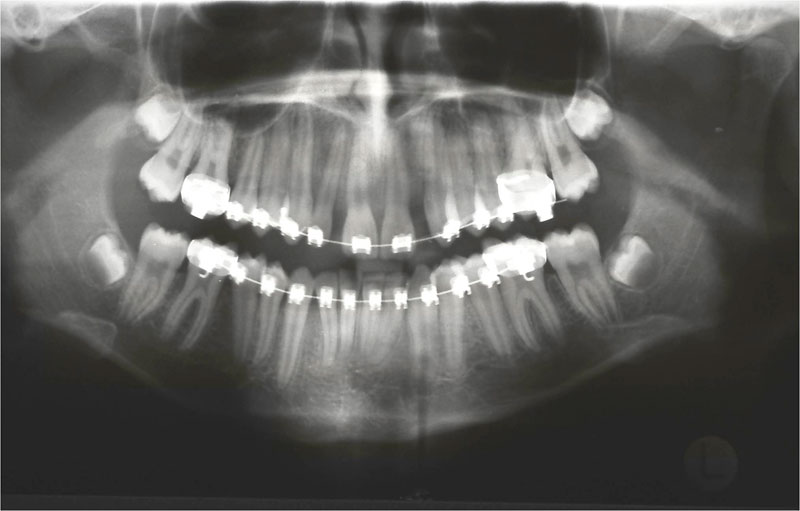

Zustand 9,5 Jahre nach Implantation